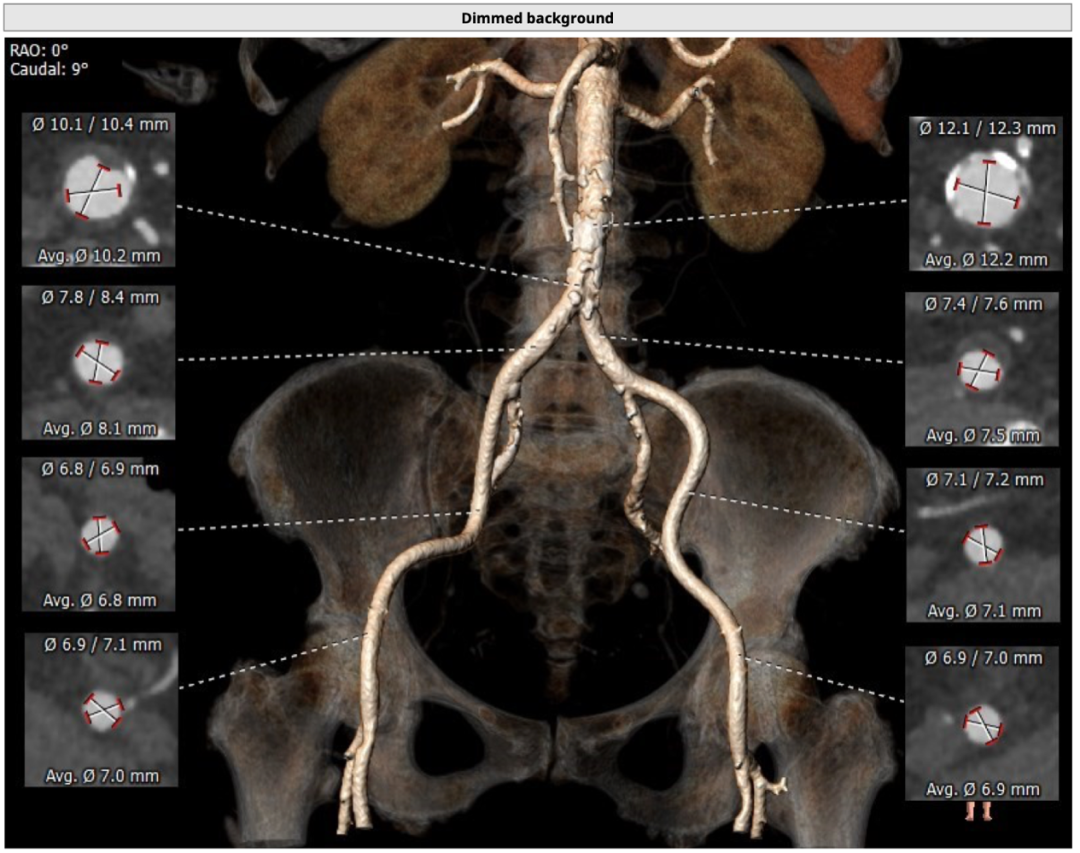

血管外周入路评估

主动脉根部评估

CT 数据显示该患者为Type1型二叶式主动脉瓣

主动脉瓣瓣环周长72.5mm,周长径23.1mm

LVOT 周长 85.1mm,周长径27.1mm

SOV:31.1mm*33.6mm*31.6mm

STJ 周长 91.9mm

无冠瓣钙化严重,HU850:448mm³

瓣环水平夹角46度